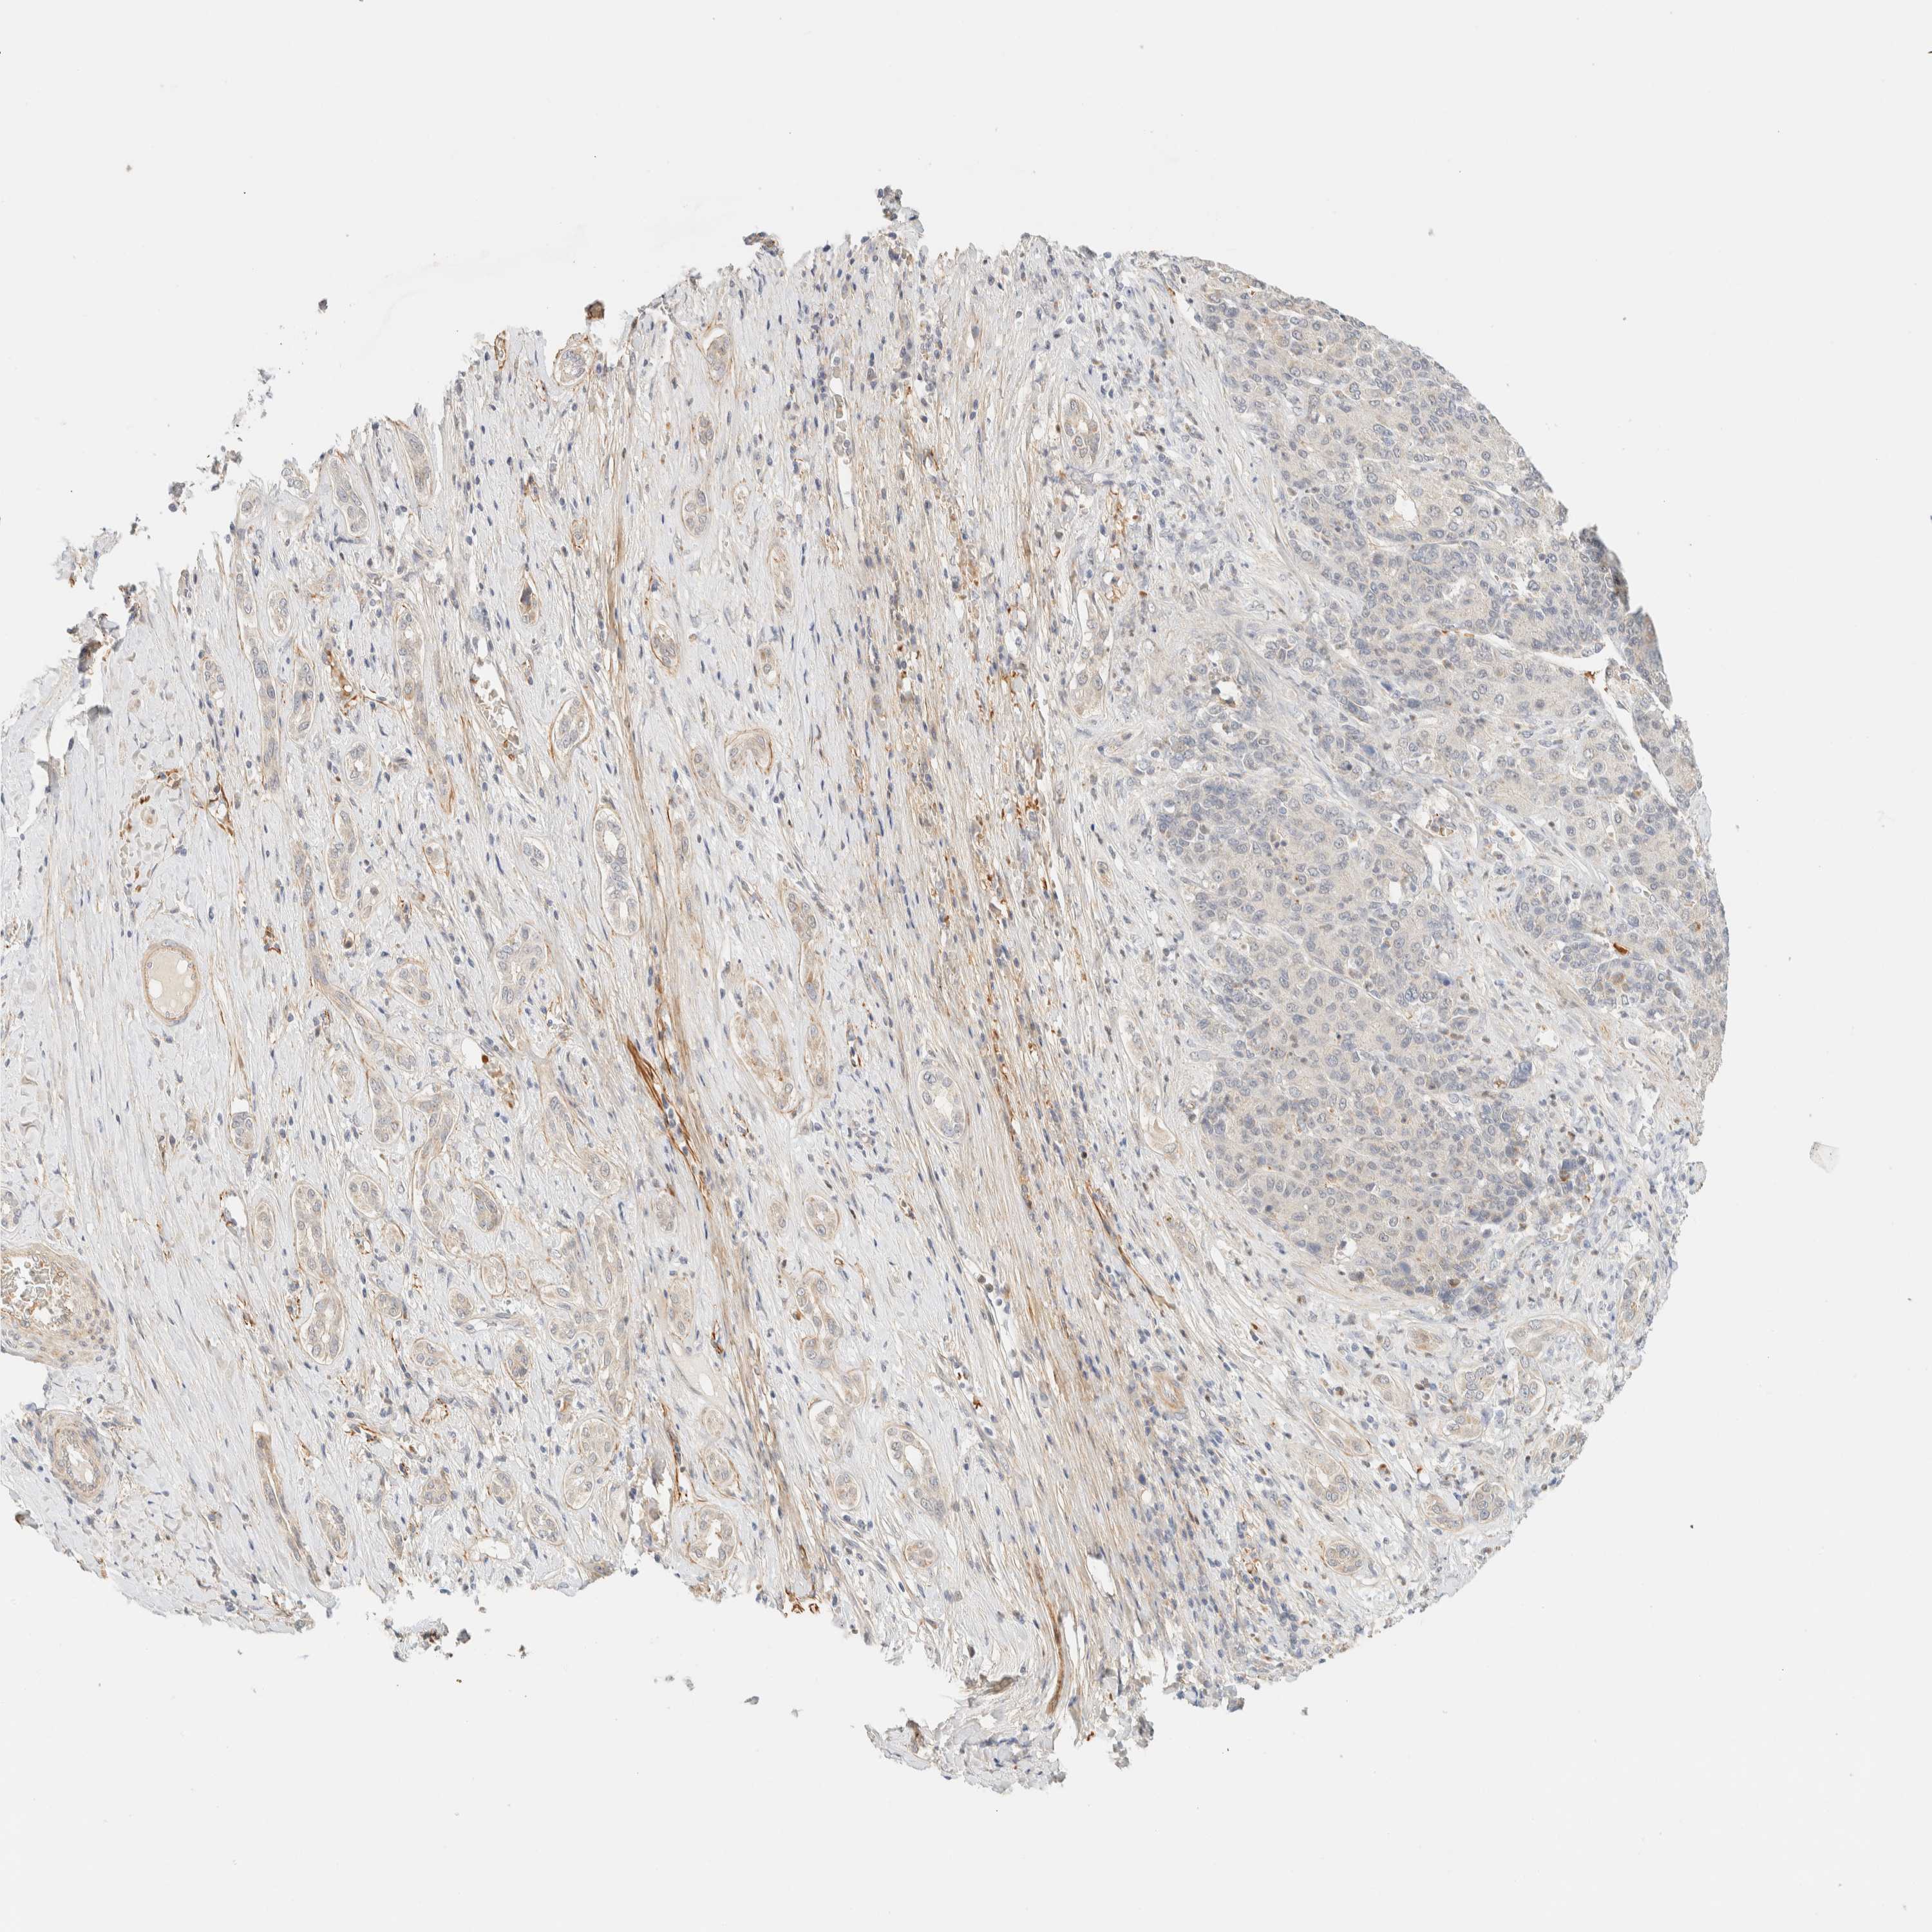

LIVER CANCER - Protein expressioni

A mouse-over function shows sample information and annotation data. Click on an image to view it in a full screen mode. Samples can be filtered based on level of antibody staining by selecting one or several of the following categories: high, medium, low and not detected. The assay and annotation is described here.

Note that samples used for immunohistochemistry by the Human Protein Atlas do not correspond to samples in the TCGA dataset.

Antibody stainingi

Antibody staining in the annotated cell types in the current human tissue is reported as not detected, low, medium, or high, based on conventional immunohistochemistry profiling in selected tissues. This score is based on the combination of the staining intensity and fraction of stained cells.

Each image is clickable and will lead to virtual microscopy that enables deeper exploration of all samples and also displays staining intensity scores, fraction scores and subcellular localization as well as patient and tissue information for each sample.

Antibody HPA012065

Staining

High

Medium

Low

Not detected

Intensity

Strong

Moderate

Weak

Negative

Quantity

>75%

75%-25%

<25%

None

Location

Nuclear

Cytoplasmic/membranous

Cytoplasmic/membranous,nuclear

Cholangiocarcinoma

Carcinoma, Hepatocellular, NOS